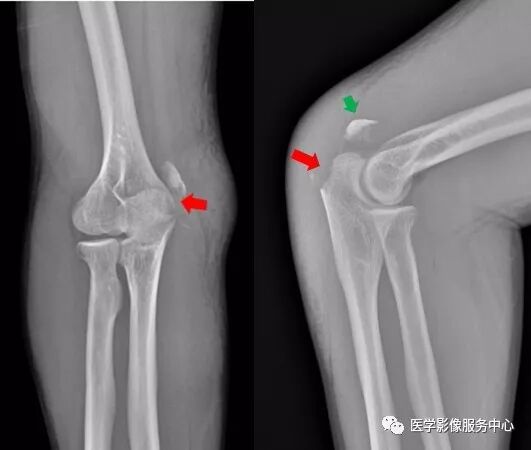

右肘关节内侧见游离骨碎片影,侧位示骨碎片位于右肘关节背侧,右尺骨近端背侧骨质部分缺如。右尺骨近端背侧撕脱性骨折。